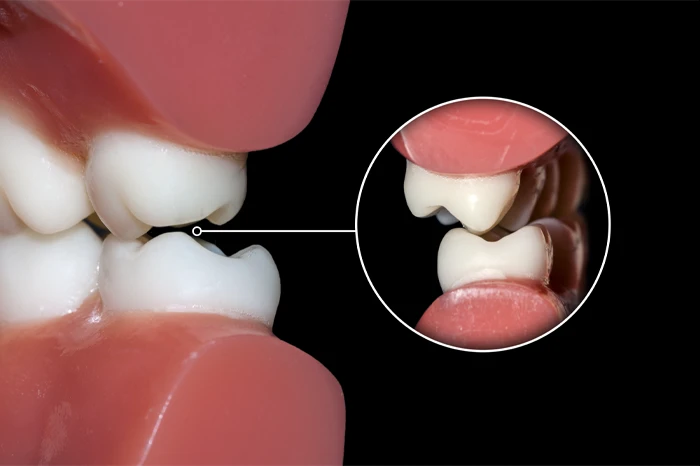

痛みの原因③ 噛み合わせの異常

歯ぎしり・食いしばりが強くなると、一部の歯だけに強く当たる状態が起こります。すると、「噛んだ時に痛い」「特定の歯だけ違和感がある 」といった症状が出てきます。

噛み合わせも関係する

さらに、歯ぎしり・食いしばりによって「噛み合わせがズレる」「一部の歯に過剰な負担がかかる」ことで、特定の角度だけ痛いという症状も出てきます。